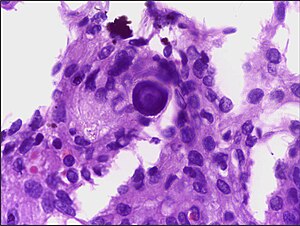

Psammoma bodies appear in benign and malignant conditions. Their presence can help focus the DDx.[1]

They are often associated with a papillary architecture.[citation needed]

Isolated psammoma bodies in smears or aspirates are an unreliable predictor of papillary carcinoma. [12]